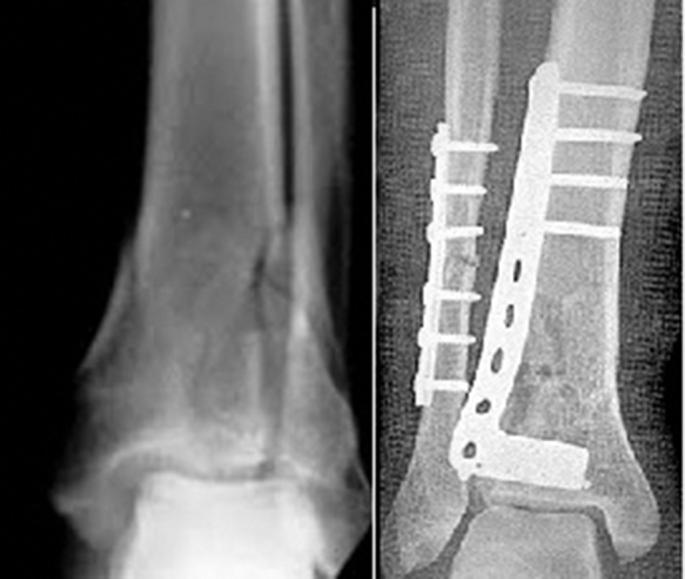

The medial plating group used medial approach (Fig. 1), including 18 patients (mean 36.2 years). Fifteen patients (83.33%) suffered from vehicular trauma. Three patients had open fractures and 16 had tibial fractures concurrent with ipsilateral fibular fracture. The mean follow-up was 6.7 months.

Fig. 1.

X-ray showed tibial plating by medial approach.

The lateral plating group used a lateral approach (Fig. 2), including 18 patients (mean 41.6 years). Thirteen patients (72.22%) suffered from vehicle-related trauma. Four had open fractures and 14 had tibial fractures concurrent with ipsilateral fibular fracture. The mean follow-up was 6.2 months. In the medial plating group, the medial plating was performed as described by Clifford et al.3 If the distal fibula was fractured, it was fixed using separate incisions. In the lateral plating group, the lateral approach was performed as described by Manninen et al.9 A vertical skin incision was made from distal fibula to the anterior margin of the fibula. The dorsal cutaneous branches of the superficial peroneal nerve were retracted and protected. The fibula was exposed, if fractured, it was fixed firstly to obtain the reference length of the tibia. The anterior muscles and neurovascular tissue were bluntly dissected from the interosseous membrane and retracted anteriorly.

Fig. 2.

X-ray showed tibial plating by lateral approach.